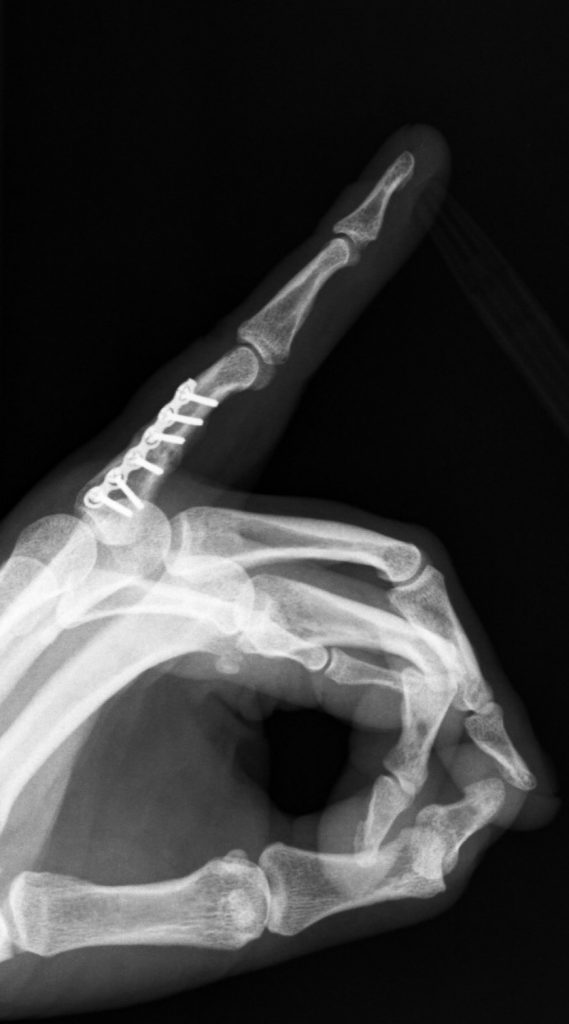

PATOLOGÍAS EN MANO Y DEDOS - FRACTURAS DE LA MANO Figura 1 - Fractura falange proximal 4º dedo

Figura 1 - Fractura falange proximal 4º dedo.(Ver también Figura 5)

Algunas fracturas pueden ser sencillas, en las que los fragmentos de huesos están alineados y estables. Otras son más complejas: son inestables y los fragmentos de hueso tienden a desplazarse: hundirse, girarse, angularse…(Figuras 1, 2 y 3).

Otras fracturas pueden precisar cirugía para reconstruir la forma y posición del hueso (reducción abierta). Una vez que los fragmentos del hueso están en su sitio, se mantienen con clavos, placas o tornillos (Figuras 5, 6 y 7).

FRACTURAS DE LA MANO Figura 5 - Osteosíntesis con placa fractura falange proximal 4º dedo

Figura 5 - Osteosíntesis con placa fractura falange proximal 4º dedo.